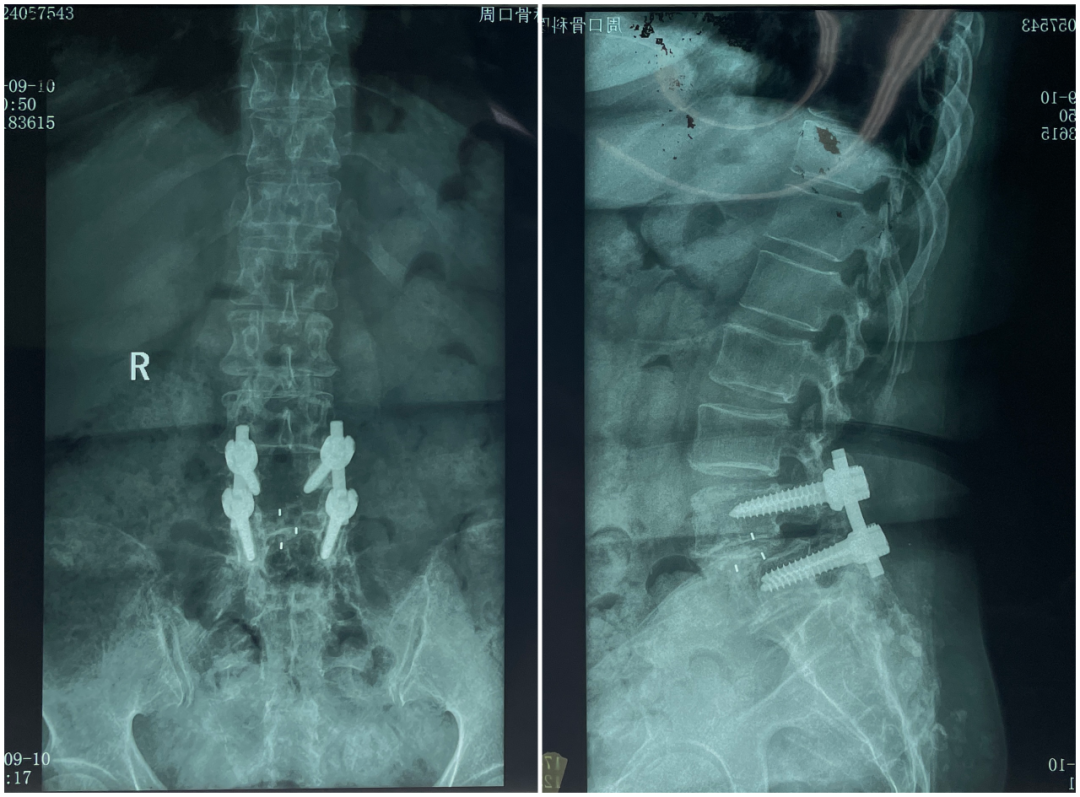

李女士,56歲。5年前施行L4/L5腰椎滑脫減壓固定椎間融合術(shù),1年前腰痛、跛行再次出現(xiàn)并進行性加重,復(fù)查發(fā)現(xiàn)L4/L5椎間不融合、椎弓根螺釘釘?shù)狼懈?、L4椎體I度滑脫,并見L3/L4椎間盤突出伴不穩(wěn)(臨椎?。?。

術(shù)前影像